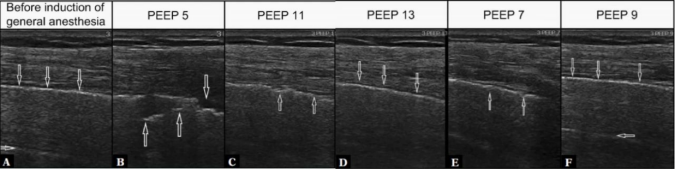

3)超声在全麻患者中的应用:超声同样适用于全麻患者的肺保护通气,通过监测胸膜线连续性、胸膜下实变等指标指导PEEP滴定。例如,麻醉诱导前肺部超声图像显示正常、高回声胸膜线和A线伪影;PEEP 5 cmH2O时胸膜线碎片化,出现小的低回声胸膜下实变(典型肺不张表现);PEEP增至11 cmH2O时胸膜下实变明显减少;PEEP 13 cmH2O再次可见正常、高回声胸膜线;降低PEEP至7 cmH2O时出现胸膜线连续性节段紊乱(肺不张初始图像);将PEEP再增加到9 cmH2O后,可见肺通气障碍逆转,正常胸膜线和A线伪影,此即为肺复张时的个体化PEEP(图3)

图片

3  有良好超声表现的肺复张

图源:J Ultrason, 2022, 22(88):e6-e11.